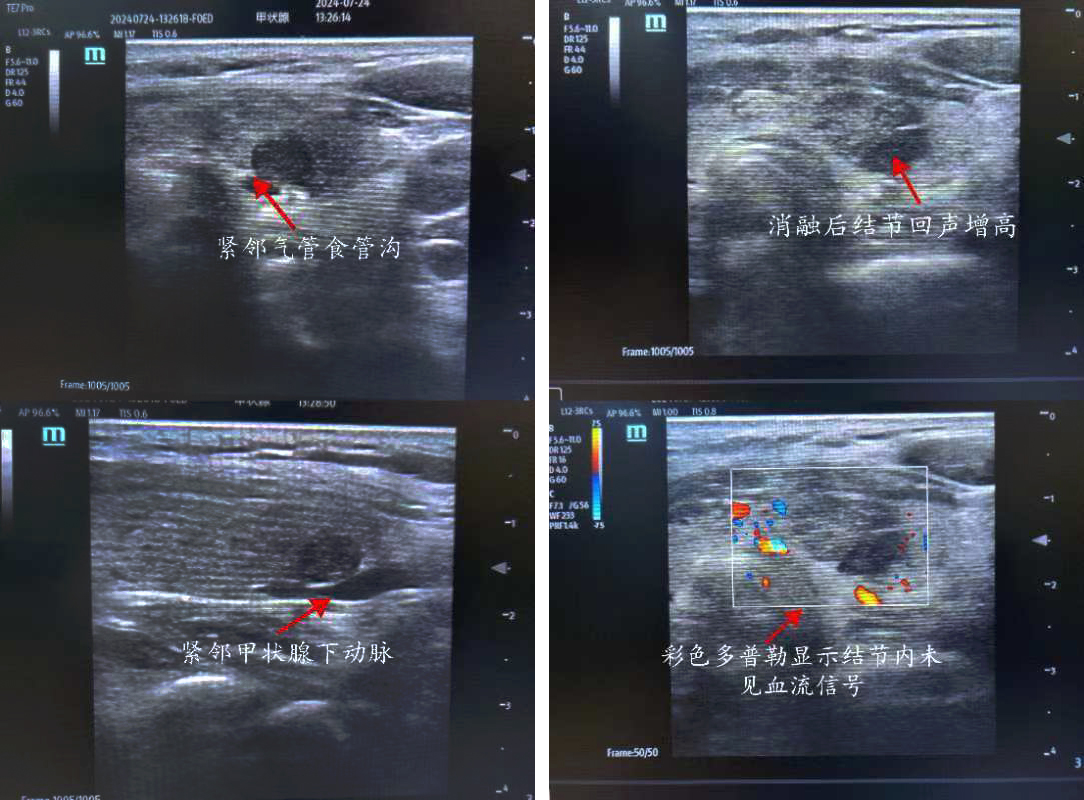

患者,女,50歲,甲狀腺彩超示:甲狀腺左側(cè)葉下極探及一約0.8*0.3cm低回聲結(jié)節(jié),界尚清,形態(tài)不規(guī)則,內(nèi)回聲不均質(zhì),內(nèi)似可見點(diǎn)狀強(qiáng)回聲,周邊及其內(nèi)可見血流信號(hào) TI-RADS 4a級(jí)。入院后行甲狀腺左側(cè)葉結(jié)節(jié)細(xì)針穿刺細(xì)胞學(xué)檢查+BRAF基因檢測(cè),結(jié)果示:考慮為濾泡上皮細(xì)胞非典型病變,BRAFV600E基因檢測(cè)未見突變。但患者左側(cè)葉4a結(jié)節(jié)位于腺體背側(cè),緊鄰氣管食管溝,與左側(cè)喉返神經(jīng)走行位置相近,患者自覺復(fù)查隨訪心理壓力大,強(qiáng)烈要求積極處理此結(jié)節(jié)。但因傳統(tǒng)手術(shù)切除治療創(chuàng)傷較大,美觀性較差,且術(shù)后可能需終身服藥,患者不愿接受手術(shù)切除。

俞景奎主任醫(yī)師、孫守毅副主任醫(yī)師及診療組詳細(xì)分析討論后,決定為患者行超聲引導(dǎo)下甲狀腺左葉結(jié)節(jié)微波消融術(shù)。對(duì)于該患者而言,行微波消融治療有兩大難點(diǎn),一是患者左葉結(jié)節(jié)位于腺體背側(cè),緊鄰左側(cè)喉返神經(jīng),消融治療易損傷喉返神經(jīng)致聲音嘶??;二是彩超下見患者左葉結(jié)節(jié)背側(cè)緊貼甲狀腺下動(dòng)脈,易出現(xiàn)血管損傷出血情況。在李峰主任和俞景奎主任醫(yī)師支持指導(dǎo)下,孫守毅副主任醫(yī)師及馬凱麗主治醫(yī)師為患者制定詳細(xì)手術(shù)方案,術(shù)中在結(jié)節(jié)與周圍重要組織結(jié)構(gòu)之間建立隔離帶,形成安全隔離區(qū)域,力爭(zhēng)將患者手術(shù)風(fēng)險(xiǎn)降到最低。最終,患者順利完成手術(shù),且術(shù)后血管和喉返神經(jīng)均無損傷,患者聲音無變化, 順利康復(fù)出院,對(duì)治療效果非常滿意。